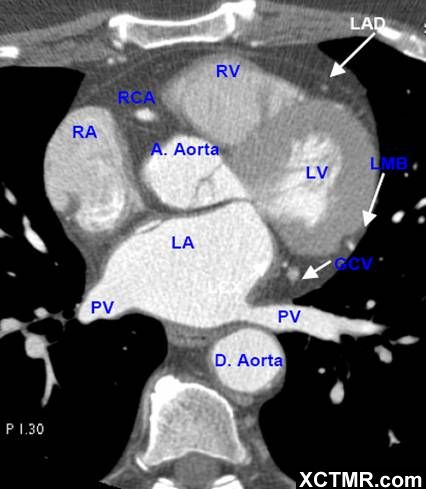

心脏CT解剖中英文对照标注(二)(图文) Cardiac Anatomy

LA - Left Atrium 左心房

RA - Right Atrium 右心房

LV - Left Ventricle 左心室

RV - Right Ventricle 右心室

A. Aorta-Ascending Aorta 升主动脉

D. Aorta-Descending Aorta 降主动脉

PV - Pulmonary Vein 肺静脉

LAD - Left Anterior Descending Artery 左前降支

LMB - Left Obtuse Marginal Branch 左边缘支(钝缘支)

RCA - Right Coronary Artery 右冠状动脉

GCV –Great Cardiac Vein 心大静脉